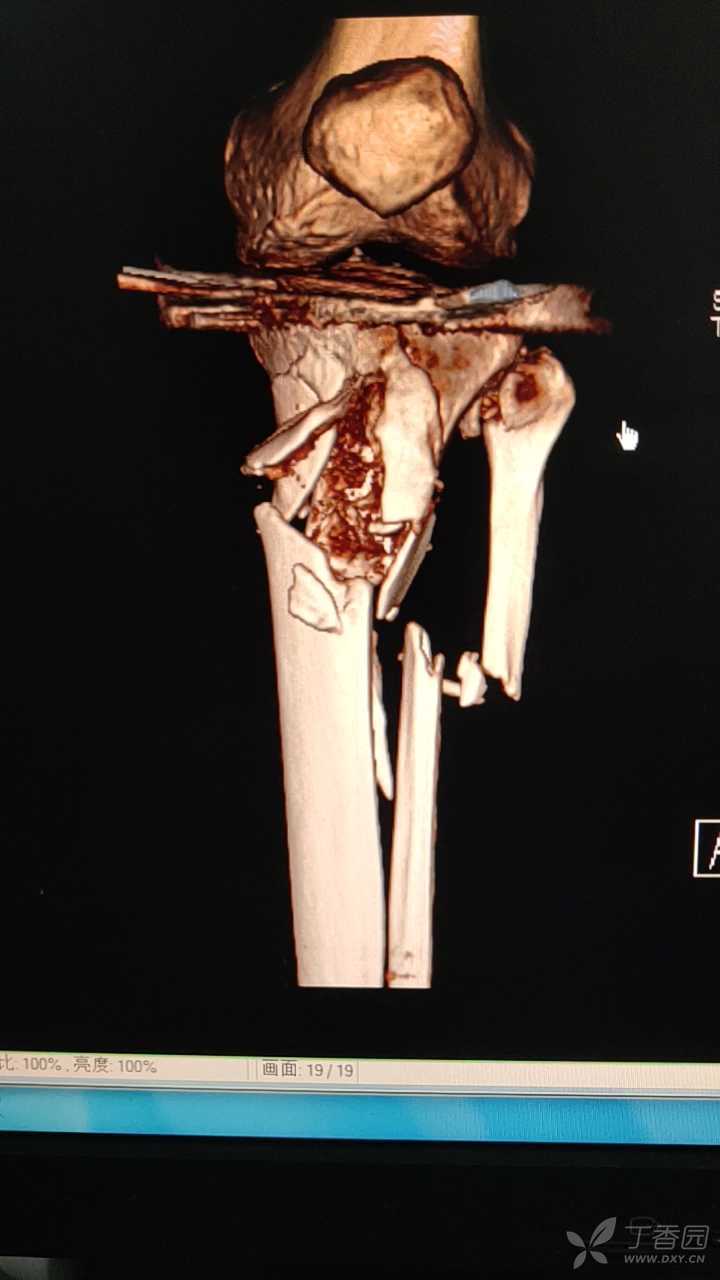

合并严重骨松的胫骨近端骨折

一例胫骨近段粉碎骨折的完整病历